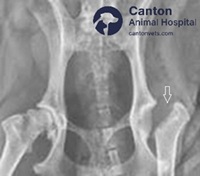

Total Hip Replacement (THR) in Dogs

What Is Total Hip Replacement (THR)?

Total Hip Replacement (THR) is a surgical procedure used to treat severe hip dysplasia, arthritis, or chronic hip pain in dogs. The procedure involves:

Removing the damaged hip joint

Replacing it with an artificial hip implant

Restoring pain-free movement and normal joint function

THR is the gold standard for treating advanced hip disease, allowing dogs to regain full range of motion and return to an active lifestyle.

How Is Total Hip Replacement Performed?

Step 1: The dog is placed under general anesthesia Step 2: The diseased femoral head (ball) and acetabulum (socket) are removed Step 3: A prosthetic femoral head and socket are securely implanted Step 4: The joint is tested for proper movement and stability Step 5: The incision is closed, and recovery begins

The entire procedure takes approximately 2-3 hours, followed by a monitored recovery.

Follow-up X-rays at 6-8 weeks to confirm healing and implant stability